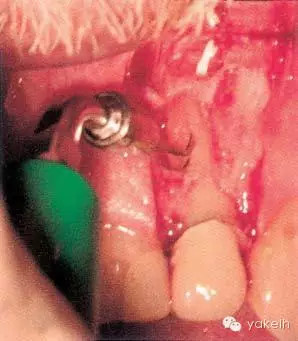

¤¤在征得患者同意后,最終選擇根管外科手術(shù)修復(fù)穿孔。局麻下翻開(kāi)三角形全厚黏骨膜瓣,充分暴露骨和根面;使用刮匙去除穿孔上覆蓋的肉芽組織,暴露穿孔和樁(圖5.4.2a);使用外科專(zhuān)用渦輪手機(jī)配以金剛砂小球鉆,去除樁的尖端;使用超聲銼去除根管末端的牙膠,并進(jìn)行根管預(yù)備(圖5.4.2b);預(yù)備后的根管與穿孔部位使用IRM嚴(yán)密封閉(圖5.4.2c);瓣復(fù)位、縫合固定,拍攝術(shù)后X線片(圖5.4.3a);3天后拆線。

圖5.4.2(a)去除肉芽組織,暴露穿孔和樁。